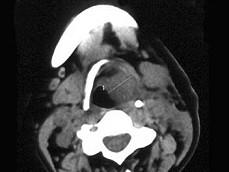

问题 女,54岁,鼻咽部异物感约3个月,PE:左侧声带固定,可见肿物,CT如图所示,应诊断为 ( )

选项 A、慢性增生性喉炎 B、增生型喉结核 C、喉癌 D、喉部血管瘤 E、喉部乳头状瘤

答案 C